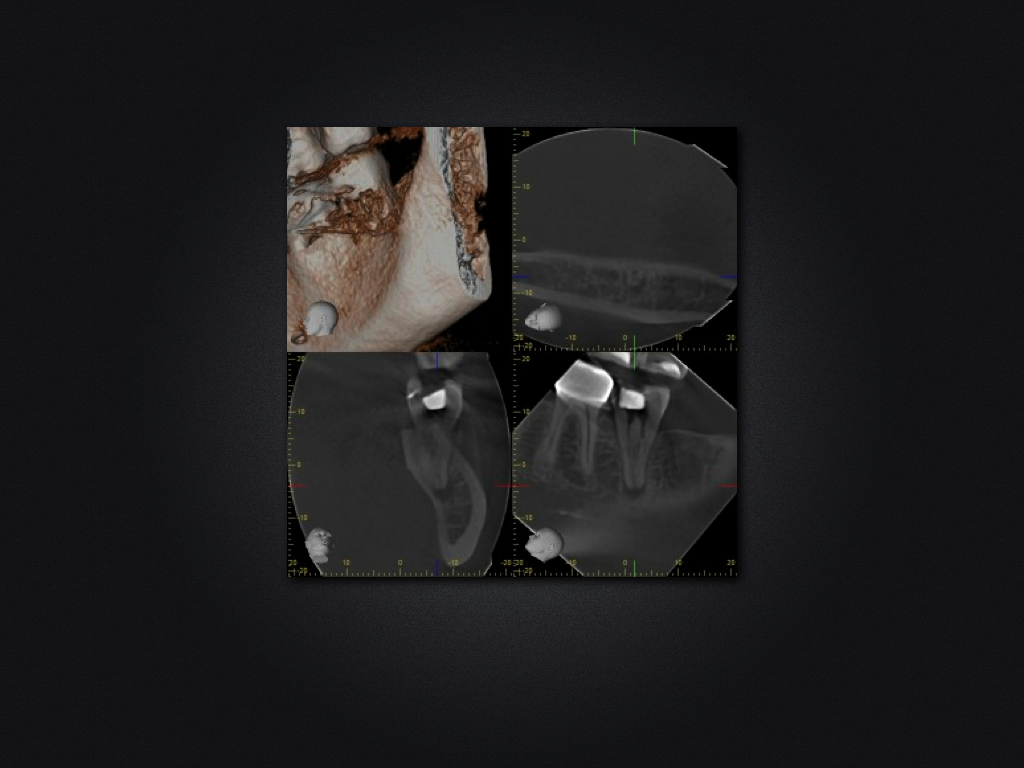

37D.005

1024 × 768

37 c-shaped